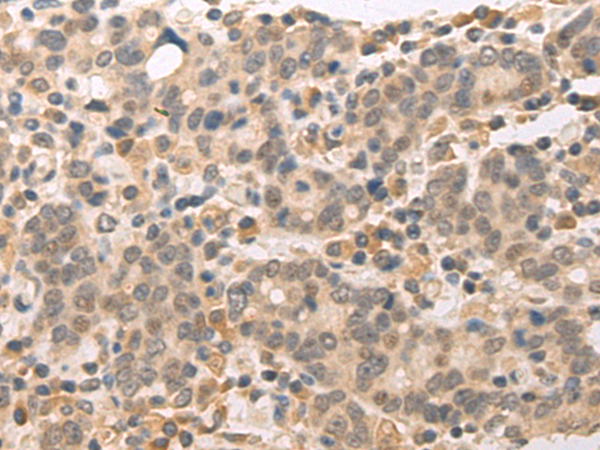

分类: 科研抗体货号: P00470别名:应用: IHC反应种属: Human